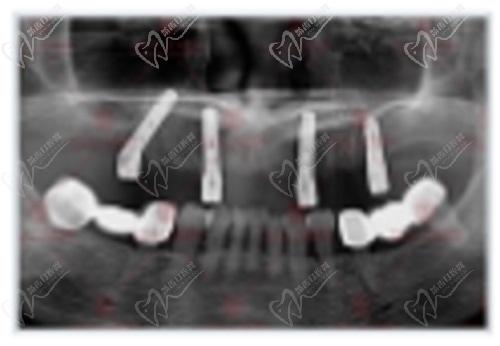

全口種植ct圖